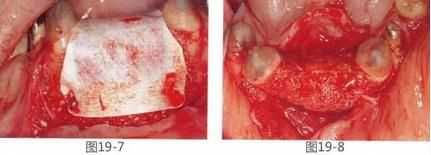

圖19-7  將非吸收性覆膜放置于黃金框架和骨移植材料上,并使用釘子固定。

圖19-8  GBR后1個(gè)月將覆膜以及黃金框架去除,這時(shí)的咬合面照。